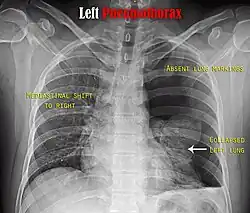

Chest X-ray showing a pneumothorax on the right (left in the image), where the absence of lung markings indicates that there is free air inside the chest -

Chest X-ray showing the features of pneumothorax on the left side of the person (right in image)

It is not unusual for the mediastinum (the structure between the lungs that contains the heart, great blood vessels, and large airways) to be shifted away from the affected lung due to the pressure differences. This is not equivalent to a tension pneumothorax, which is determined mainly by the constellation of symptoms, hypoxia, and shock.[16]

The size of the pneumothorax (i.e. the volume of air in the pleural space) can be determined with a reasonable degree of accuracy by measuring the distance between the chest wall and the lung. This is relevant to treatment, as smaller pneumothoraces may be managed differently. An air rim of 2 cm means that the pneumothorax occupies about 50% of the hemithorax.[18] British professional guidelines have traditionally stated that the measurement should be performed at the level of the hilum (where blood vessels and airways enter the lung) with 2 cm as the cutoff,[18] while American guidelines state that the measurement should be done at the apex (top) of the lung with 3 cm differentiating between a "small" and a "large" pneumothorax.[38] The latter method may overestimate the size of a pneumothorax if it is located mainly at the apex, which is a common occurrence.[18] The various methods correlate poorly but are the best easily available ways of estimating pneumothorax size.[18][22] CT scanning (see below) can provide a more accurate determination of the size of the pneumothorax, but its routine use in this setting is not recommended.[38]